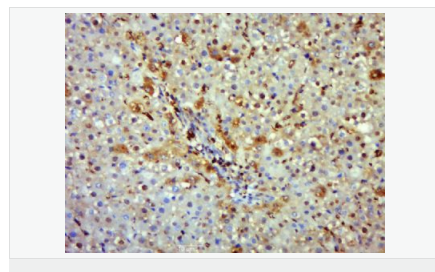

| 英文名稱 | iNos/Nos-2 |

| 中文名稱 | 一氧化氮合成酶-2(誘導型)抗體 |

| 產(chǎn)品應用 | WB=1:500-2000 IHC-P=1:100-500 IHC-F=1:100-500 Flow-Cyt=1μg/Test ICC=1:100-500 IF=1:100-500 (石蠟切片需做抗原修復) not yet tested in other applications. optimal dilutions/concentrations should be determined by the end user. |

| 產(chǎn)品介紹 | Nitric oxide (NO) is an inorganic, gaseous free radical that carries a variety of messages between cells. Vasorelaxation, neurotransmission and cytotoxicity can all be potentiated through cellular response to NO. NO production is mediated by members of the nitric oxide synthase (NOS) family. NOS catalyzes the oxidization of L-arginine to produce L-citrulline and NO. Two constitutive isoforms, brain or neuronal NOS (b or nNOS, type I) & endothelial cell NOS (eNOS, type III), and one inducible isoform (iNOS, type II), have been cloned. All NOS isoforms contain calmodulin, nicotinamide adenine dinucleotide phosphate (NADPH), flavin adenine dinucleotide (FAD), and flavin mononucleotide (FMN) binding domains. Nitric oxide synthase is expressed in liver, macrophages, hepatocytes, synoviocytes, stimulated glial cells and smooth muscle cells. Cytokines such as interferon-gamma (IFN), tumor necrosis factor (TNF), interleukin-1 and -2, and lipopolysaccarides (LPS) cause an increase in iNOS mRNA, protein, and activity levels. Protein kinase C-stimulating agents exhibit the same effect on iNOS activity. After cytokine induction, iNOS exhibits a delayed activity response which is then followed by a significant increase in NO production over a long period of time. Human iNOS is regulated by calcium/calmodulin (in contrast with mouse NOS2). Function: Produces nitric oxide (NO) which is a messenger molecule with diverse functions throughout the body. In macrophages, NO mediates tumoricidal and bactericidal actions. Also has nitrosylase activity and mediates cysteine S-nitrosylation of cytoplasmic target proteins such COX2. Subunit: Homodimer. Binds SLC9A3R1. Tissue Specificity: Expressed in the liver, retina, bone cells and airway epithelial cells of the lung. Not expressed in the platelets. Similarity: Belongs to the NOS family. Contains 1 FAD-binding FR-type domain. Contains 1 flavodoxin-like domain. SWISS: P35228 Gene ID: 4843 Database links: Entrez Gene: 4843 Human Entrez Gene: 18126 Mouse Omim: 163730 Human SwissProt: P35228 Human SwissProt: P29477 Mouse Unigene: 709191 Human Unigene: 2893 Mouse Unigene: 10400 Rat Important Note: This product as supplied is intended for research use only, not for use in human, therapeutic or diagnostic applications. 合成與降解(Synthesis and Degradation) 催化生物體內(nèi)一氧化氮(NO)生成的酶。分神經(jīng)型一氧化氮合成的酶(nNOS or NOS-1)、誘導型一氧化氮合成的酶(iNOS or NOS-2)、內(nèi)皮型一氧化氮合成的酶(eNOS or NOS-3)。 |